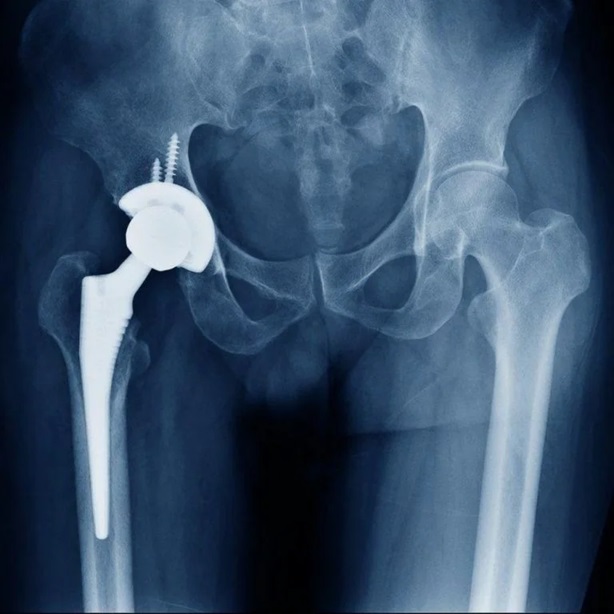

HIP Replacement Surgery

Let’s consult Dr (Lt.Col.) Manoj Kumar for successful HIP Replacement Surgery & treatment in Mathura.